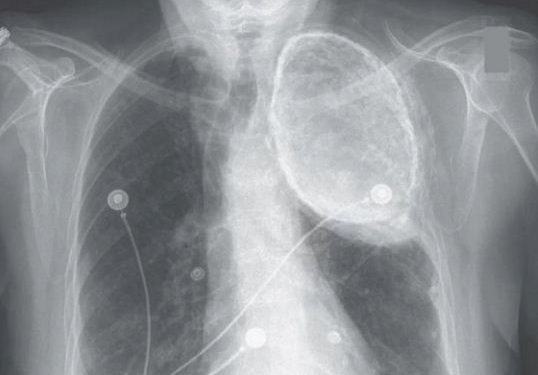

A mulher de 86 anos foi ao médico por causa de uma dor ardente no peito e no estômago. Ela foi diagnosticada com refluxo ácido, e seus sintomas melhoraram depois que ela começou o tratamento para a condição. Mas enquanto ela estava no hospital, ela fez uma radiografia de tórax que mostrava algo incomum: havia uma área opaca e turva na parte superior do pulmão esquerdo.

Esta área nebulosa era preocupante para seus médicos, porque poderia significar que ela tinha acumulação de fluidos no espaço entre a parede do peito e seu pulmão, conhecida como a cavidade pleural. Em pessoas com certas condições, sangue ou pus podem se acumular nesta área.

Quando o óleo é injetado na cavidade pleural, os vasos sanguíneos e vasos linfáticos na área inicialmente absorvem parte do óleo, disse Koratala. No momento em que o tratamento estava em uso, os médicos muitas vezes tinham de “encher” esta parte do pulmão com óleo até que ele entrasse em colapso, disse ele. Mas ao longo do tempo, as membranas na cavidade deixariam de absorver o óleo, provavelmente devido a danos ao tecido causados pelo óleo, disse Koratala. Isso permitiu que o óleo permanecesse na cavidade pleural, mantendo o pulmão em colapso. Depois de muitos anos, alguns depósitos de cálcio ocorreria na área, e a massa de petróleo se estabilizaria, disse Koratala.

O achado de oleotórax neste paciente foi acidental já que não estava lhe causando nenhum sintoma, e não estava relacionado ao seu refluxo ácido, disseram os médicos.